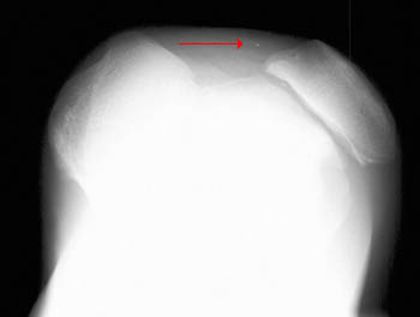

髌骨骨折

髌骨脱位

胫骨平台骨折